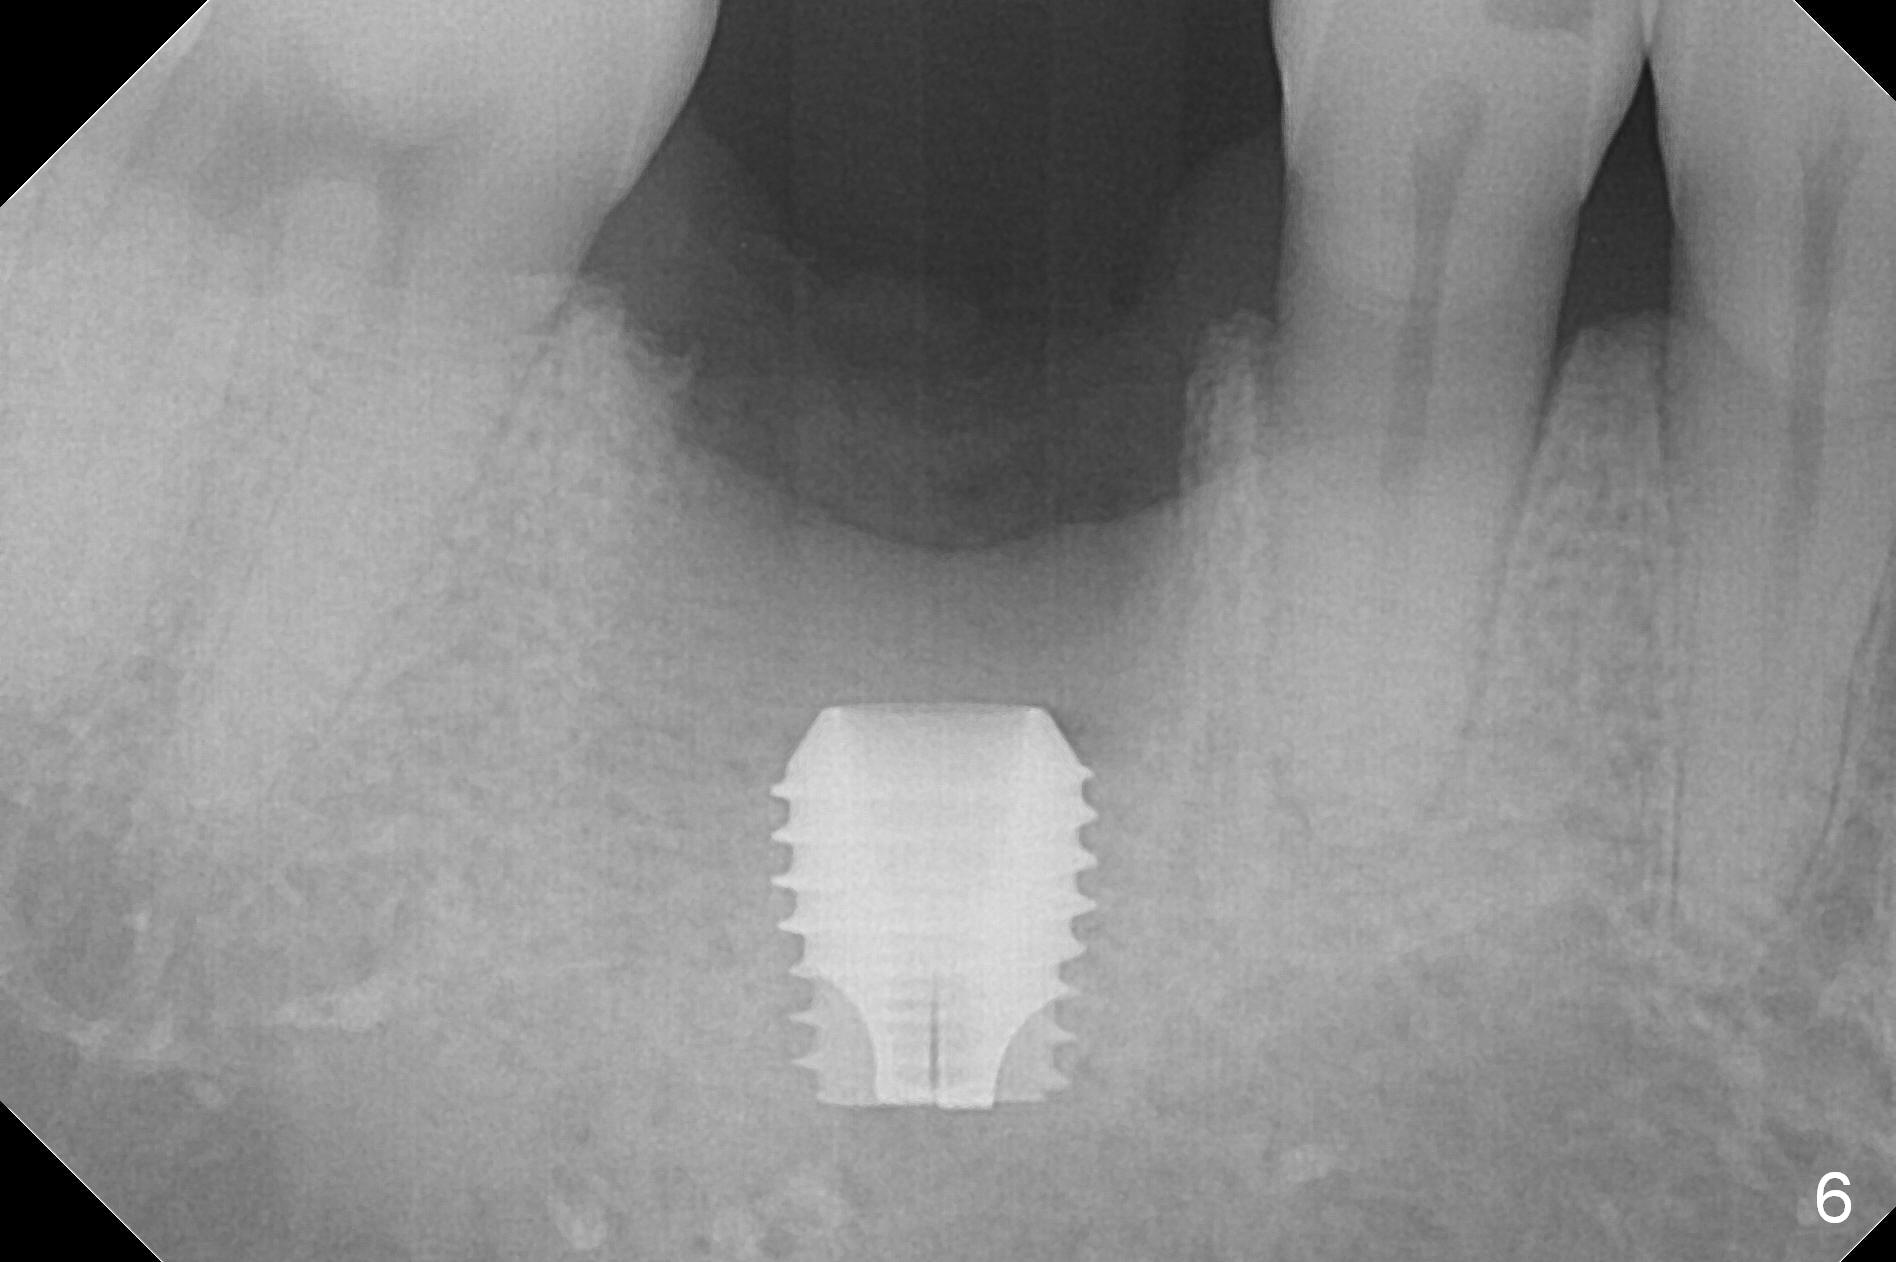

After extraction of the tooth #30 with Class V furcation involvement (Fig.1 (>),2 (L: lingual)), initial osteotomy depth is 8 mm with infiltration anesthesia, but a parallel pin is able to be inserted for 16 mm without pain (Fig.3). There is oozing from the osteotomy. Osteotomy increases in diameter with depth at 8 mm (Fig.4 (3.8 mm drill),5 (5.3 mm tap)). As the Inferior Alveolar Canal (IAC) is indistinct with increased pain during osteotomy, a 5.9x6 mm implant is placed with >50 Ncm following Septocaine infiltration (Fig.6). When bone graft (Fig.7 *) and 7.8x5.5(6) mm abutment (Fig.7,8) are placed, panoramic X-ray is taken (Fig.9). There appears to be a thick layer of spongy bone in the posterior mandible between the red and yellow dashed lines (Fig.5,9). Panoramic X-ray and/or CBCT should be taken if preop PA does not reveal IAC. This patient seems to be a bruxer. There are mandibular tori. Bone loss (furcation involvement) is not proportional to his oral hygiene status. Functional loading (progressive) should be delayed due to bruxism and the short implant.